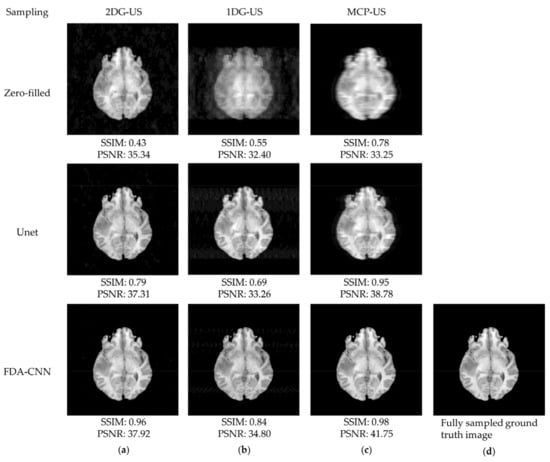

4.1. BraTs 2020-T1 Dataset